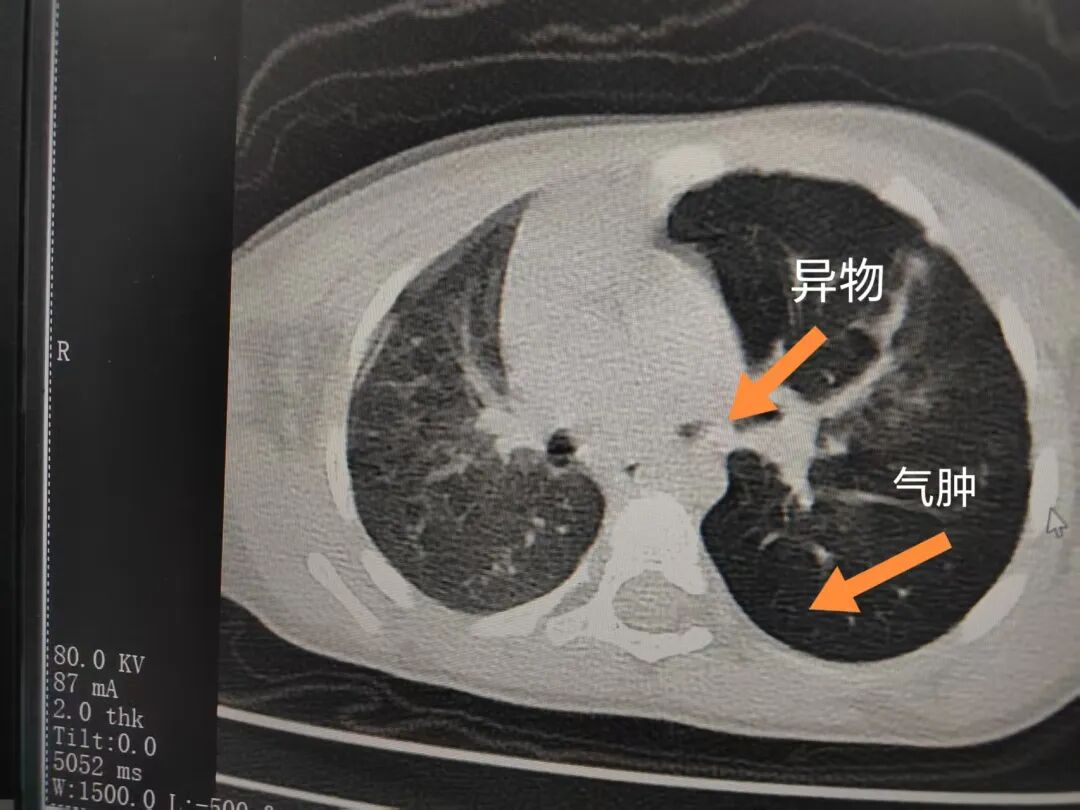

三天后(11月13日),趙寶出現(xiàn)高熱、咳喘加重,家長(zhǎng)著急了,再次帶他來(lái)到醫(yī)院。CT檢查顯示左肺過(guò)度充氣,左肺上下葉支氣管主干見(jiàn)不規(guī)則高密度影,左肺上葉可見(jiàn)大片狀密度增高影,縱隔窗實(shí)變,提示為“左側(cè)支氣管內(nèi)異物并繼發(fā)性改變,左肺上葉舌段肺膨脹不全”。

市二院小兒呼吸內(nèi)科團(tuán)隊(duì)迅速為患兒制定了周密的手術(shù)方案,并很快安排了氣管鏡探查。術(shù)中,主治醫(yī)師田慧等憑借嫻熟的氣管鏡操作技術(shù)成功將異物大塊板栗取出。由于板栗在氣管內(nèi)存留時(shí)間較長(zhǎng),質(zhì)地軟糯易碎,大大增加了手術(shù)難度。檢查還發(fā)現(xiàn),異物停留部位的氣管黏膜已出現(xiàn)充血紅腫、糜爛,導(dǎo)致患兒住院時(shí)間相應(yīng)延長(zhǎng)。此次事件給趙寶的家庭帶來(lái)了不小的驚嚇與擔(dān)憂(yōu),也再次為廣大家長(zhǎng)敲響了警鐘。

市二院小兒呼吸內(nèi)科副主任楊亞娟介紹,異物誤入氣道可能導(dǎo)致氣道阻塞,嚴(yán)重時(shí)可引發(fā)窒息,甚至危及生命。若異物進(jìn)入支氣管,造成不完全堵塞,可引起阻塞性肺氣腫;如完全堵塞支氣管,則可能導(dǎo)致肺組織萎縮,形成肺不張。此外,若異物存留時(shí)間較長(zhǎng),或?yàn)橹参镄援愇铮菀缀喜⒓?xì)菌感染,產(chǎn)生膿性分泌物,進(jìn)而發(fā)展為肺炎。她強(qiáng)調(diào),盡早診斷并取出異物,是減少并發(fā)癥、降低病死率的關(guān)鍵。